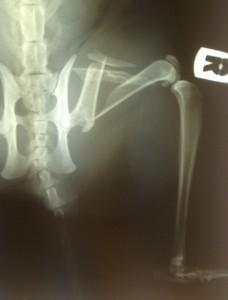

– multifragmentarni – kominutivni zlomi pri visokoenergetskih poškodbah, kjer se kost razleti na več kot dva dela (Slika 2);